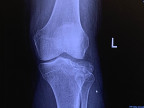

on April 14, 2023 I was in surgery for a comminuted fracture of the lateral left tibia. That’s less than a week ago.

they’ve put me on blood thinners for 12 days. The basic prognosis is no weight-bearing for eight weeks.